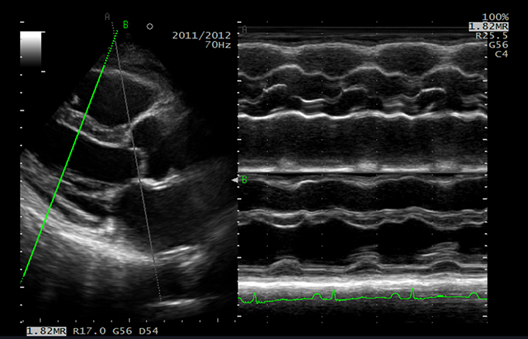

D.S.D. muestra una imagen en tiempo real y su contraparte en cámara lenta lado a lado en una pantalla. El movimiento rápido de la válvula se puede observar en detalle.

El modo M se puede mostrar utilizando cualquier orientación del cursor.

El movimiento de la pared y la válvula se puede comparar desde varios ángulos en el mismo latido cardíaco.